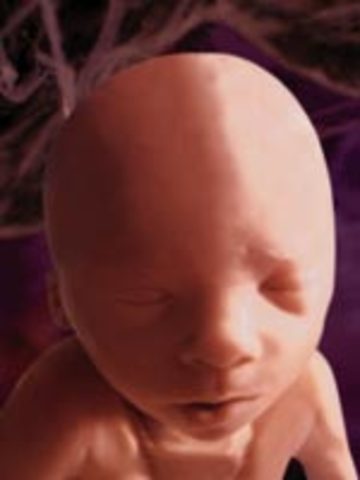

• Week 38: Development is complete

Week 38: Development is complete

The length of the baby is now 20 inches and weighs 7.5 pounds. The body fat of the baby is gaining by the ounce. The development of the baby is beginning to complete. By now, the baby will have a full head of hair.

Facts: -Most babies are born head first

-Wrinkled skin is becoming smooth